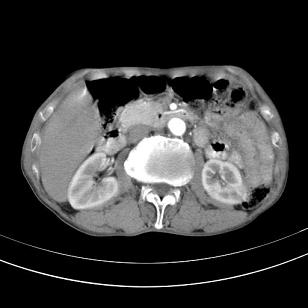

标题: 男,65岁,反复右上腹痛, [打印本页]

标题: 男,65岁,反复右上腹痛,

胃镜提示十二指肠占位